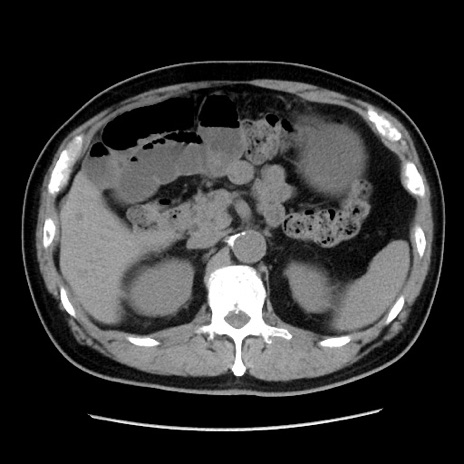

症例16(横断像)

【症例】 70歳代男性

【主訴】 腹痛、嘔吐

【現病歴】 約1ヶ月前より間欠的に腹痛と嘔吐あり、当院消化器内科を受診したところCTで多発する肝臓のLDAを指摘され、精査中であった。以降は消化器症状は安定していたが、2日前より嘔気と腹痛があり、同日より排便・排ガスが消失した。改善認めず、 本日、救急外来を受診した。

【既往歴】 大腸ポリープ切除後。

【身体所見】意識清明・会話良好、BT 36.3℃、BP 127/80mmHg、 P 80bpm、腹部:膨満あり、平坦・軟、上腹部正中および下腹部正中に圧痛あり、反跳痛なし、筋性防御なし。

【データ】WBC 7200、CRP 0.77